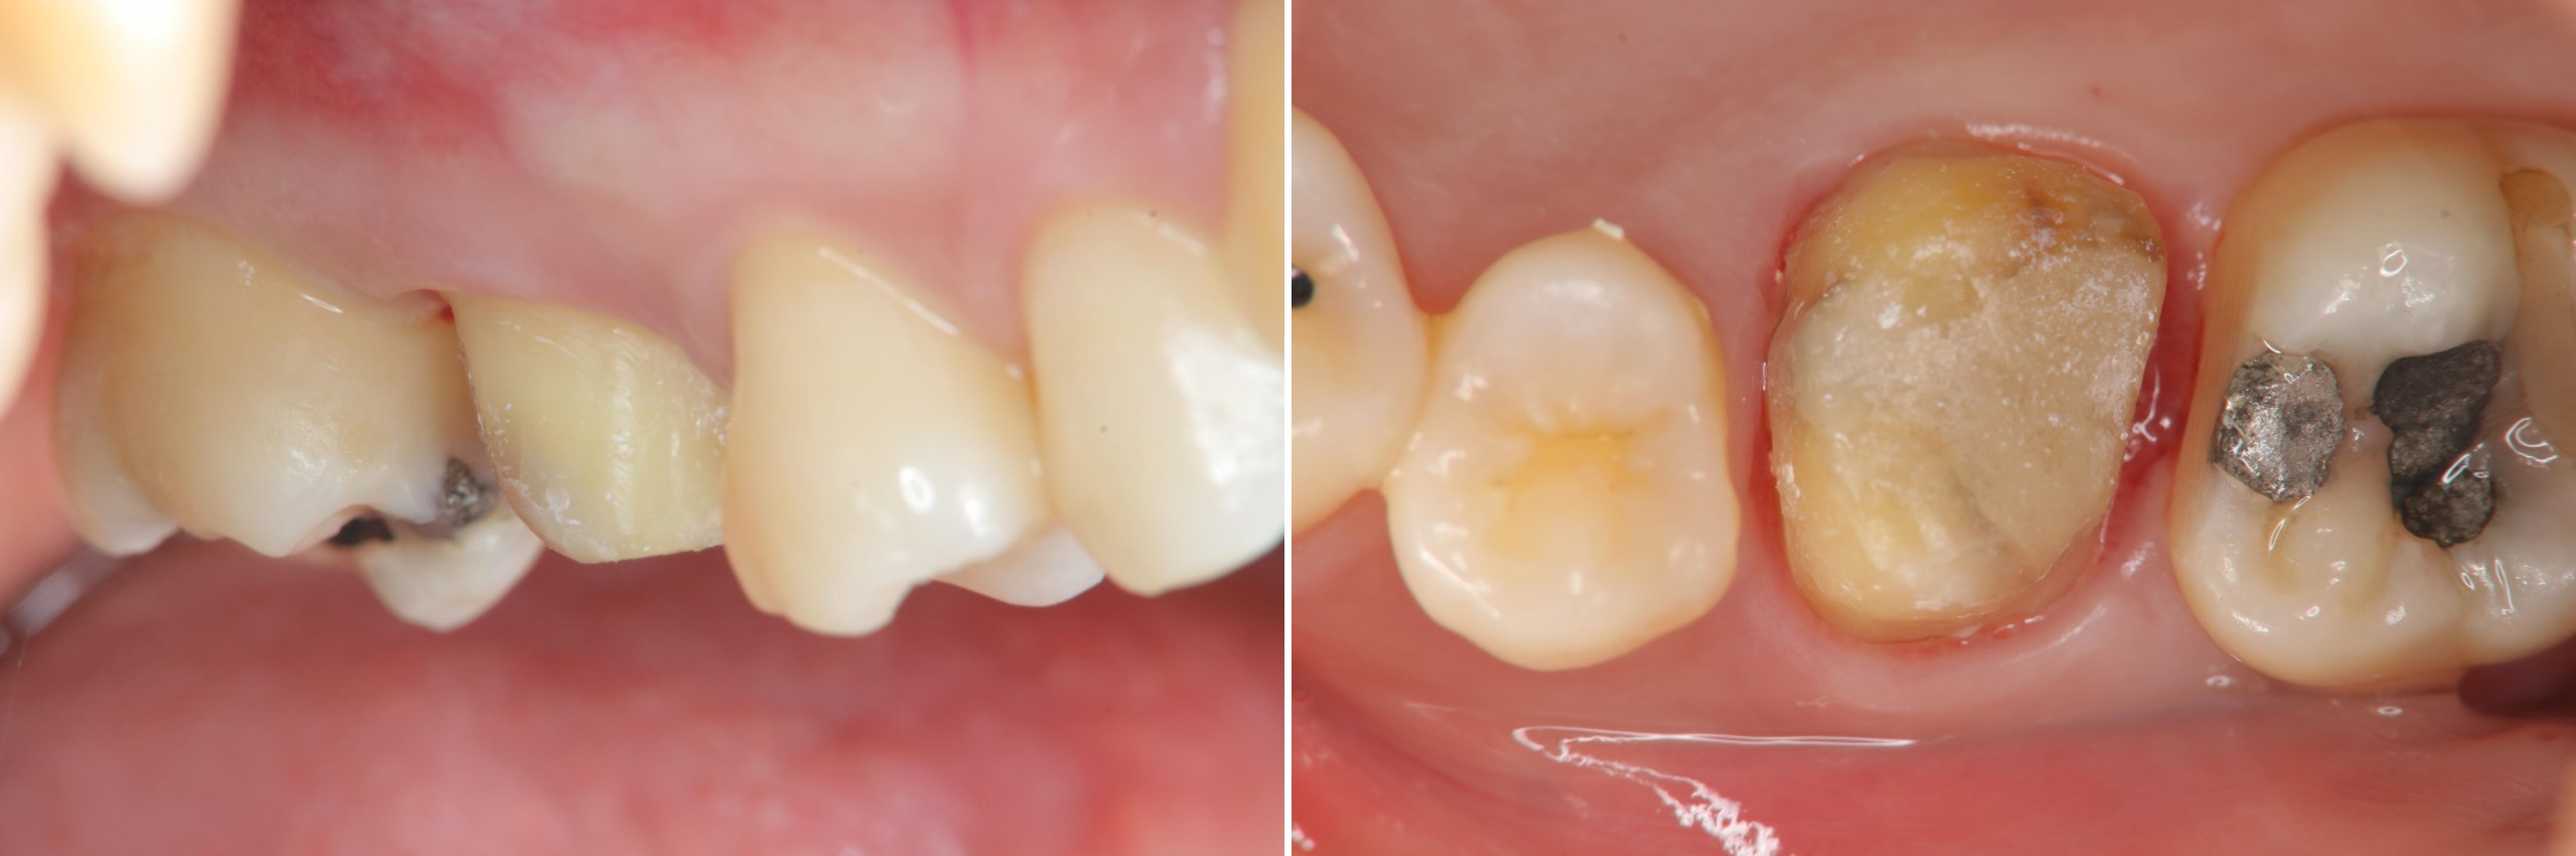

水雷射牙齦切除手術

膺復前評估牙齦、牙齒狀態